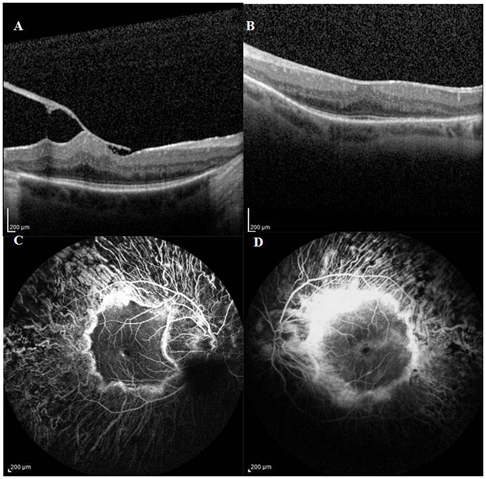

A 58-year old Caucasian male with a past diagnosis of retinitis pigmentosa (RP) presented with 4 month history of decreasing in vision in right eye (OD). Visual acuity (VA) was 20/30-2 in OU (both eyes). Anterior segment examination was unremarkable except for sulcus placed posterior chamber intraocular lens. Fundus examination OU showed vitreous syneresis, pale optic disc with diffuse retinal pigment epithelial (RPE) atrophy, retinal arteriolar attenuation, and bone-spicule like pigment in all four quadrants of the retina with an island of pigmented area in the macula. There was an epiretinal membrane (ERM) with retinal thickening in the macula of OD. There were no retinal hemorrhages or exudates in macula OU. Heidelberg-Spectralis optical coherence tomography (OCT) demonstrated the epiretinal membrane (ERM) with cystoid intraretinal retinal edema (Figure 1A) in OD and marked thinning of the retinal pigment epithelium in the left eye (OS) (Figure 1B). Central foveal thickness was 447 microns in OD and 357 microns in OS.  Fundus fluorescein angiography (FA) revealed a circular area of hyperfluorescence in the macula OU, with areas of hyperfluorescence in early phases followed by leakage in late phases (Figure 1C) confirming presence of macular edema in OD. There was no evidence of angiographic macular leakage in OS (Figure 1D). He had bilateral cochlear implant surgery done few years ago for hearing loss. He was diagnosed with Usher’s syndrome type I with ERM and cystoid macular edema (CME) in right eye. Treatment options were observation, pars plana vitrectomy with membrane peeling and oral acetazolamide. He was followed by observation. He also was advised to take oral vitamin A and was informed to avoid intake of excessive vitamin E. However, he will be considered for surgical correction of ERM if there is further decrease in the vision.

Figure 1.Heidelberg-Spectralis OCT of right eye demonstrating epiretinal membrane with retinal edema due to vitreomacular traction band (1A) and of the left eye showing blunting of the foveal contour with thinning of the RPE (1B). Fundus Fluorescein angiography showing a circular area of hyperfluorescence in the macula of both eyes (1C, D) and a pinpoint area of hyperfluorescence inferior to the fovea of the right eye (1C) leading to macular edema and areas of no leakage in the parafoveal region of the left eye (1D).